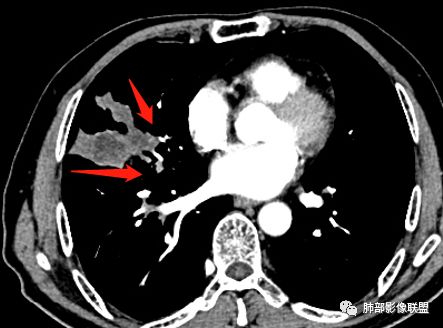

住院4天后行胸部增强CT

静脉期

老年男性,因“咳嗽咳痰1月余。”入院。病程中咳嗽咳痰,咳黄白痰,间断咯少许鲜红色痰血。PPD阳性。胸CT:右肺中叶外侧段支气管管腔阻塞,大片实性病变,病灶边缘光滑,部分边缘膨隆,可见分叶,肺门及纵隔可见肿大淋巴结,并可见钙化。增强可见病灶明显强化,而且延迟强化明显,病灶内多发低密度区,内见血管影,血管变细、部分血管破坏。考虑恶性病变可能性大,鉴别慢性肉芽肿性病变。

胸CT:跨叶大肿块,主体在中叶,右中叶外侧段支气管阻塞,病灶部分边缘膨隆,可见分叶,部分边缘平直,肺门及纵隔可见肿大淋巴结。增强病灶不均匀强化,延迟强化明显,病灶内多发低密度区,内见血管飘浮,部分血管变细、模糊。考虑:恶性病变可能性大,大细胞?淋巴瘤?鉴别慢性肉芽肿性病变。

右肺中叶软组织肿块,外围向内生长,叶间胸膜向前内移位,肿块近肺门侧跨叶,中叶外侧段支气管截断,密度不均匀,双侧肺门及隆突下见肿大淋巴结,增强后呈中度不均质强化,肺动脉供血,多发坏死区,边界尚清,坏死区域内见结构,结合病史考虑恶性,鉴别诊断1结核,爬行征是沿支气管树分布,外宽,内窄,周围有卫星灶,内气管狭窄后扩张,此例沿叶间胸膜长轴分布,气管有截断,不典型。2炎性肉芽肿,符合的地方下方层面增强后延迟性轻度环形强化,不符临床无发热等急性感染病史,实验室指标不符,病灶周围渗出及慢性炎性改变有,不明显。

墨西哥仙人掌征---结核        影像上结核灶,粗大的均匀枝干,推测是支气管囊状扩张引起的,在非支气管区,形成圆形坏死囊群;如果这些坏死比较稀薄,又遇到扩张支气管,就会形成粗大的“墨西哥仙人掌”。结核引起的支气管近端炎症纤维化,可以造成支气管阻塞,从而将干酪样坏死物封堵在管腔内。仙人掌主干内部应该是干酪为主,稀薄的,具有流动性,时间久了会出现钙化。

结核坏死与鳞癌鉴别有一点是结核坏死没有方向性,鳞癌有。鳞癌靠近支气管近端部分,血供容易维持,不易坏死,所以坏死靠外侧。而结核干酪样坏死,把一定体积的流动性坏死物,包裹起来,什么形状最省料?坏死物包裹,表面积最省的自然是圆球形,而遇到支气管,坏死物一多,就把支气管撑大了。包裹物是就地取材,扩张的支气管就成了包裹结构。